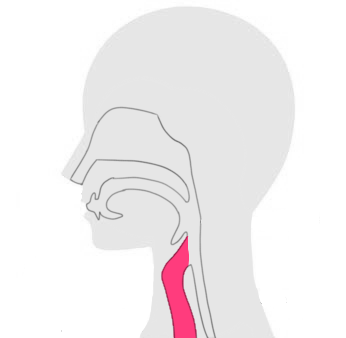

喉頭がんの「初期症状や、原因、治療方法など」は以下からご参考ください。

喉頭がんだけに限らず、がん治療にて根治を目指す場合、重要となってくるのは、早期段階による治療です。

がんのステージに関係なく行える治療方法であり、喉頭がんが含めおおよそ全身の癌に対応することが可能です。